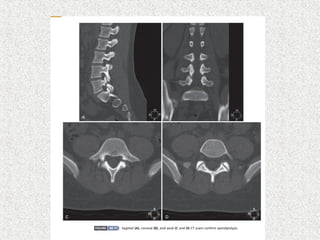

 MRI

 HRCT

 LS spineX-ray  AP  Lat  Lat flexion/extension  Oblique if suspecting spondylolysis  MRI  SPECT  HRCT